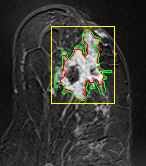

We tested the algorithm by varying the number of markers between and . Fig 2 describes the segmentation results obtained using different numbers of markers. This plot indicates that markers were found to be optimal using this segmentation approach, yielding satisfactory results.

where refers to the ROIs segmented by our algorithm and is tumor area as determined by manual segmentation. Table 1 summarizes the segmentation accuracy achieved using the proposed method for all 106 cases. The average dice coefficient was found to be 0.780.17 and average Jaccard index was 0.670.21. Fig 3 demonstrate four sample segmentation outputs which are overlaid on manual segmentations provided by two radiologists. It can be seen, that the proposed method could accurately segment the lesions with some marginal errors for medium to large tumors. However, for cases comprising disjoint lesions, the method failed to segment all small lesions and in some cases incorrectly labeled healthy tissue as lesions. This is because in some cases there is a high degree of overlap in the intensity distributions of healthy breast tissue and lesions, and the ROI drawn by the radiologist is very large in the case of disjoint lesions, in order to cover the entire area over which multiple lesions are distributed.